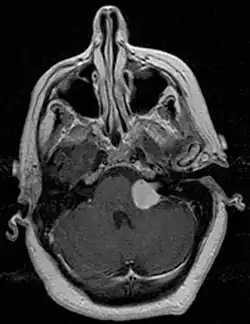

Zespół kąta mostowo-móżdżkowego

Zespół kąta mostowo-móżdżkowego – zespół objawów spowodowany obecnością guza w okolicy kąta mostowo-móżdżkowego. Najczęstszym guzem w tej okolicy są nerwiaki osłonkowe nerwu przedsionkowego, inne częste zmiany to oponiaki albo torbiele epidermoidalne, rzadkimi przyczynami są guzy przerzutowe, tętniaki, torbiele pajęczynówki, nerwiaki osłonkowe nerwu V.